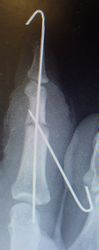

30歳男。東京都八丈島

2014年12月29日,ワイヤーに左示指を巻き込まれて不全切断受傷。〇〇病院を受診し,直ちに△△病院に救急ヘリ搬送され,形成外科で緊急手術(再接着術)となったが,生着せず,手掌部で切断⇒断端形成の予定だったが,患者の叔母(東京在住)がカンボジアで湿潤治療をしているKEN CLINICの奥澤先生と知り合いだったため,当科で一度診てもらったほうがいいとアドバイスされ,セカンドオピニオンで当科を受診。

当初はラップで被覆(ワイヤーのためにプラスモイストではうまく覆えなかった)。1月21日,22日にワイヤー抜去。3月に入ってから突出した骨を骨鉗子で切除(無麻酔で大丈夫だった)。3月19日,八丈島に戻った。